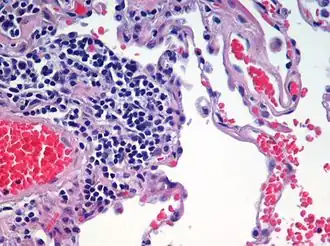

Lung tissue affected by emphysema using H&E stain

Asthma, bronchiectasis, and chronic obstructive pulmonary disease (COPD) that includes chronic bronchitis, and emphysema, are all obstructive lung diseases characterised by airway obstruction. This limits the amount of air that is able to enter alveoli because of constriction of the bronchial tree, due to inflammation. Obstructive lung diseases are often identified because of symptoms and diagnosed with pulmonary function tests such as spirometry.

Many obstructive lung diseases are managed by avoiding triggers (such as dust mites or smoking), with symptom control such as bronchodilators, and with suppression of inflammation (such as through corticosteroids) in severe cases. A common cause of chronic bronchitis, and emphysema, is smoking; and common causes of bronchiectasis include severe infections and cystic fibrosis. The definitive cause of asthma is not yet known, but it has been linked to other atopic diseases.[74][92]

The breakdown of alveolar tissue, often as a result of tobacco-smoking leads to emphysema, which can become severe enough to develop into COPD. Elastase breaks down the elastin in the lung's connective tissue that can also result in emphysema. Elastase is inhibited by the acute-phase protein, alpha-1 antitrypsin, and when there is a deficiency in this, emphysema can develop. With persistent stress from smoking, the airway basal cells become disarranged and lose their regenerative ability needed to repair the epithelial barrier. The disorganised basal cells are seen to be responsible for the major airway changes that are characteristic of COPD, and with continued stress can undergo a malignant transformation. Studies have shown that the initial development of emphysema is centred on the early changes in the airway epithelium of the small airways.[93] Basal cells become further deranged in a smoker's transition to clinically defined COPD.[93]